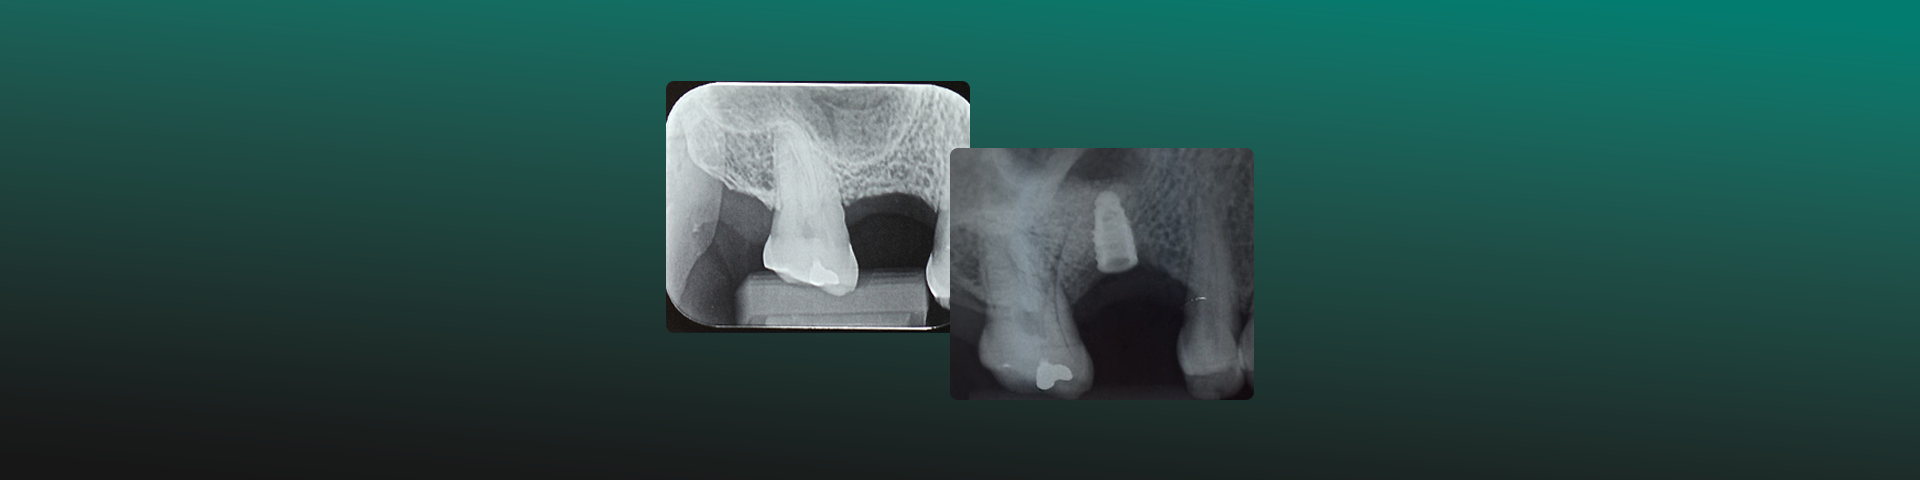

Reabilitação maxilar anterior com Sticky Bone

Autores: Prof. Dr. Helder Hirabara, Prof. Flavio Menoli e Prof. Dr. Ricardo Alves Matheus. Objetivo Clínico Promover um aumento da espessura óssea vestibular da maxila valendo-se de biomaterial sintético associado a agregados leucoplaquetários autólogos. A reconstrução da arquitetura de pré-maxilas severa ou moderadamente reabsorvidas é fundamental para uma reabilitação anterior mais previsível, pois permitirá […]